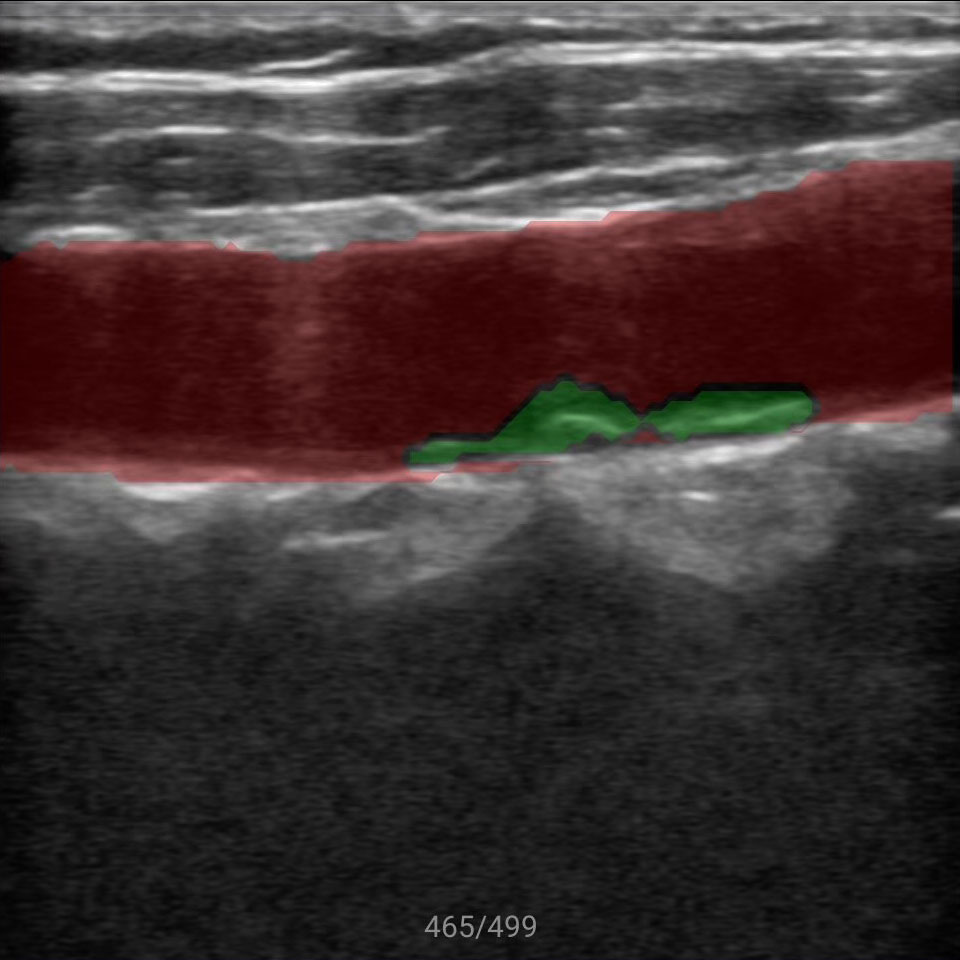

原始的超声图像像天书一样,除了专业超声医生谁都看不懂,新名医率先实现了针对超声实时动态图像的特定目标、多目标识别,准确率超过93%,超声AI数据集规模、识别准确率、移动端工程实现能力业内领先。

传统超声的多普勒测量非常繁琐,需要设置大量参数手工操作,新名医全球首创一键多普勒测量,AI自动找到血管、自动计算出12项血流动力学参数,让复杂的超声变得像血压计一样,读数就可知道异常,提示粥样动脉硬化、血管狭窄、易损斑块、流速异常等多种脑梗风险。

智能手持超声提供覆盖全身的优异图像